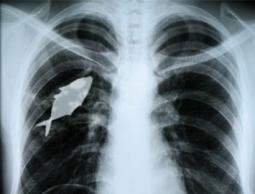

وقال ثلاثة أطباء عملوا في غرفة الطوارئ بمستشفى ناصر إن إصابات جرحاهم بطلقات نارية كانت في الغالب في الرأس أو القلب أو الرئتين.